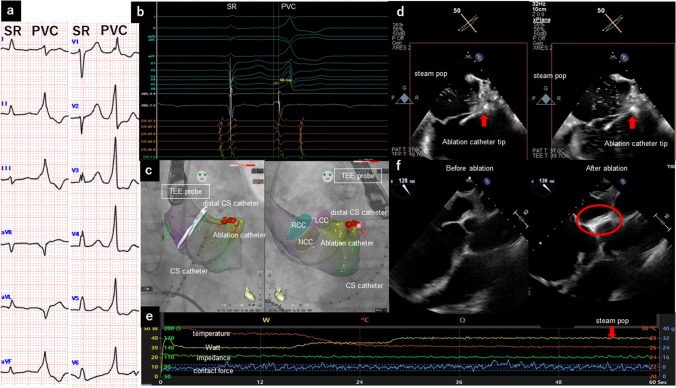

Silent steam pop detected by transesophageal echocardiography for premature ventricular contractions originating from the aortomitral continuity.

通过经食道超声心动图检测到源自主动脉连续性的室性早搏的无声蒸汽爆鸣。